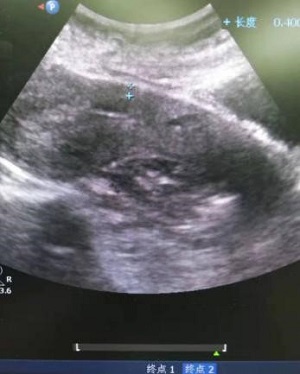

34岁的欧女士来自安仁县,因“停经55天,阴道流血4天,发现切口妊娠2天”于8月22日由门诊以“切口妊娠”收住入院。B超检查提示,剖腹产切口处15x14x11mm孕囊,内见卵黄囊,距离子宫浆膜层4mm,血流丰富。考虑切口妊娠。MRI提示:子宫中段前壁见切口凹陷,有26x15mm大小孕囊附着,附着处16mm肌层变薄,最薄处4mm,子宫前壁与腹壁粘连。诊断:子宫切口妊娠,子宫前壁与腹壁粘连。

超声像                                       MRI影像

术后超声声像